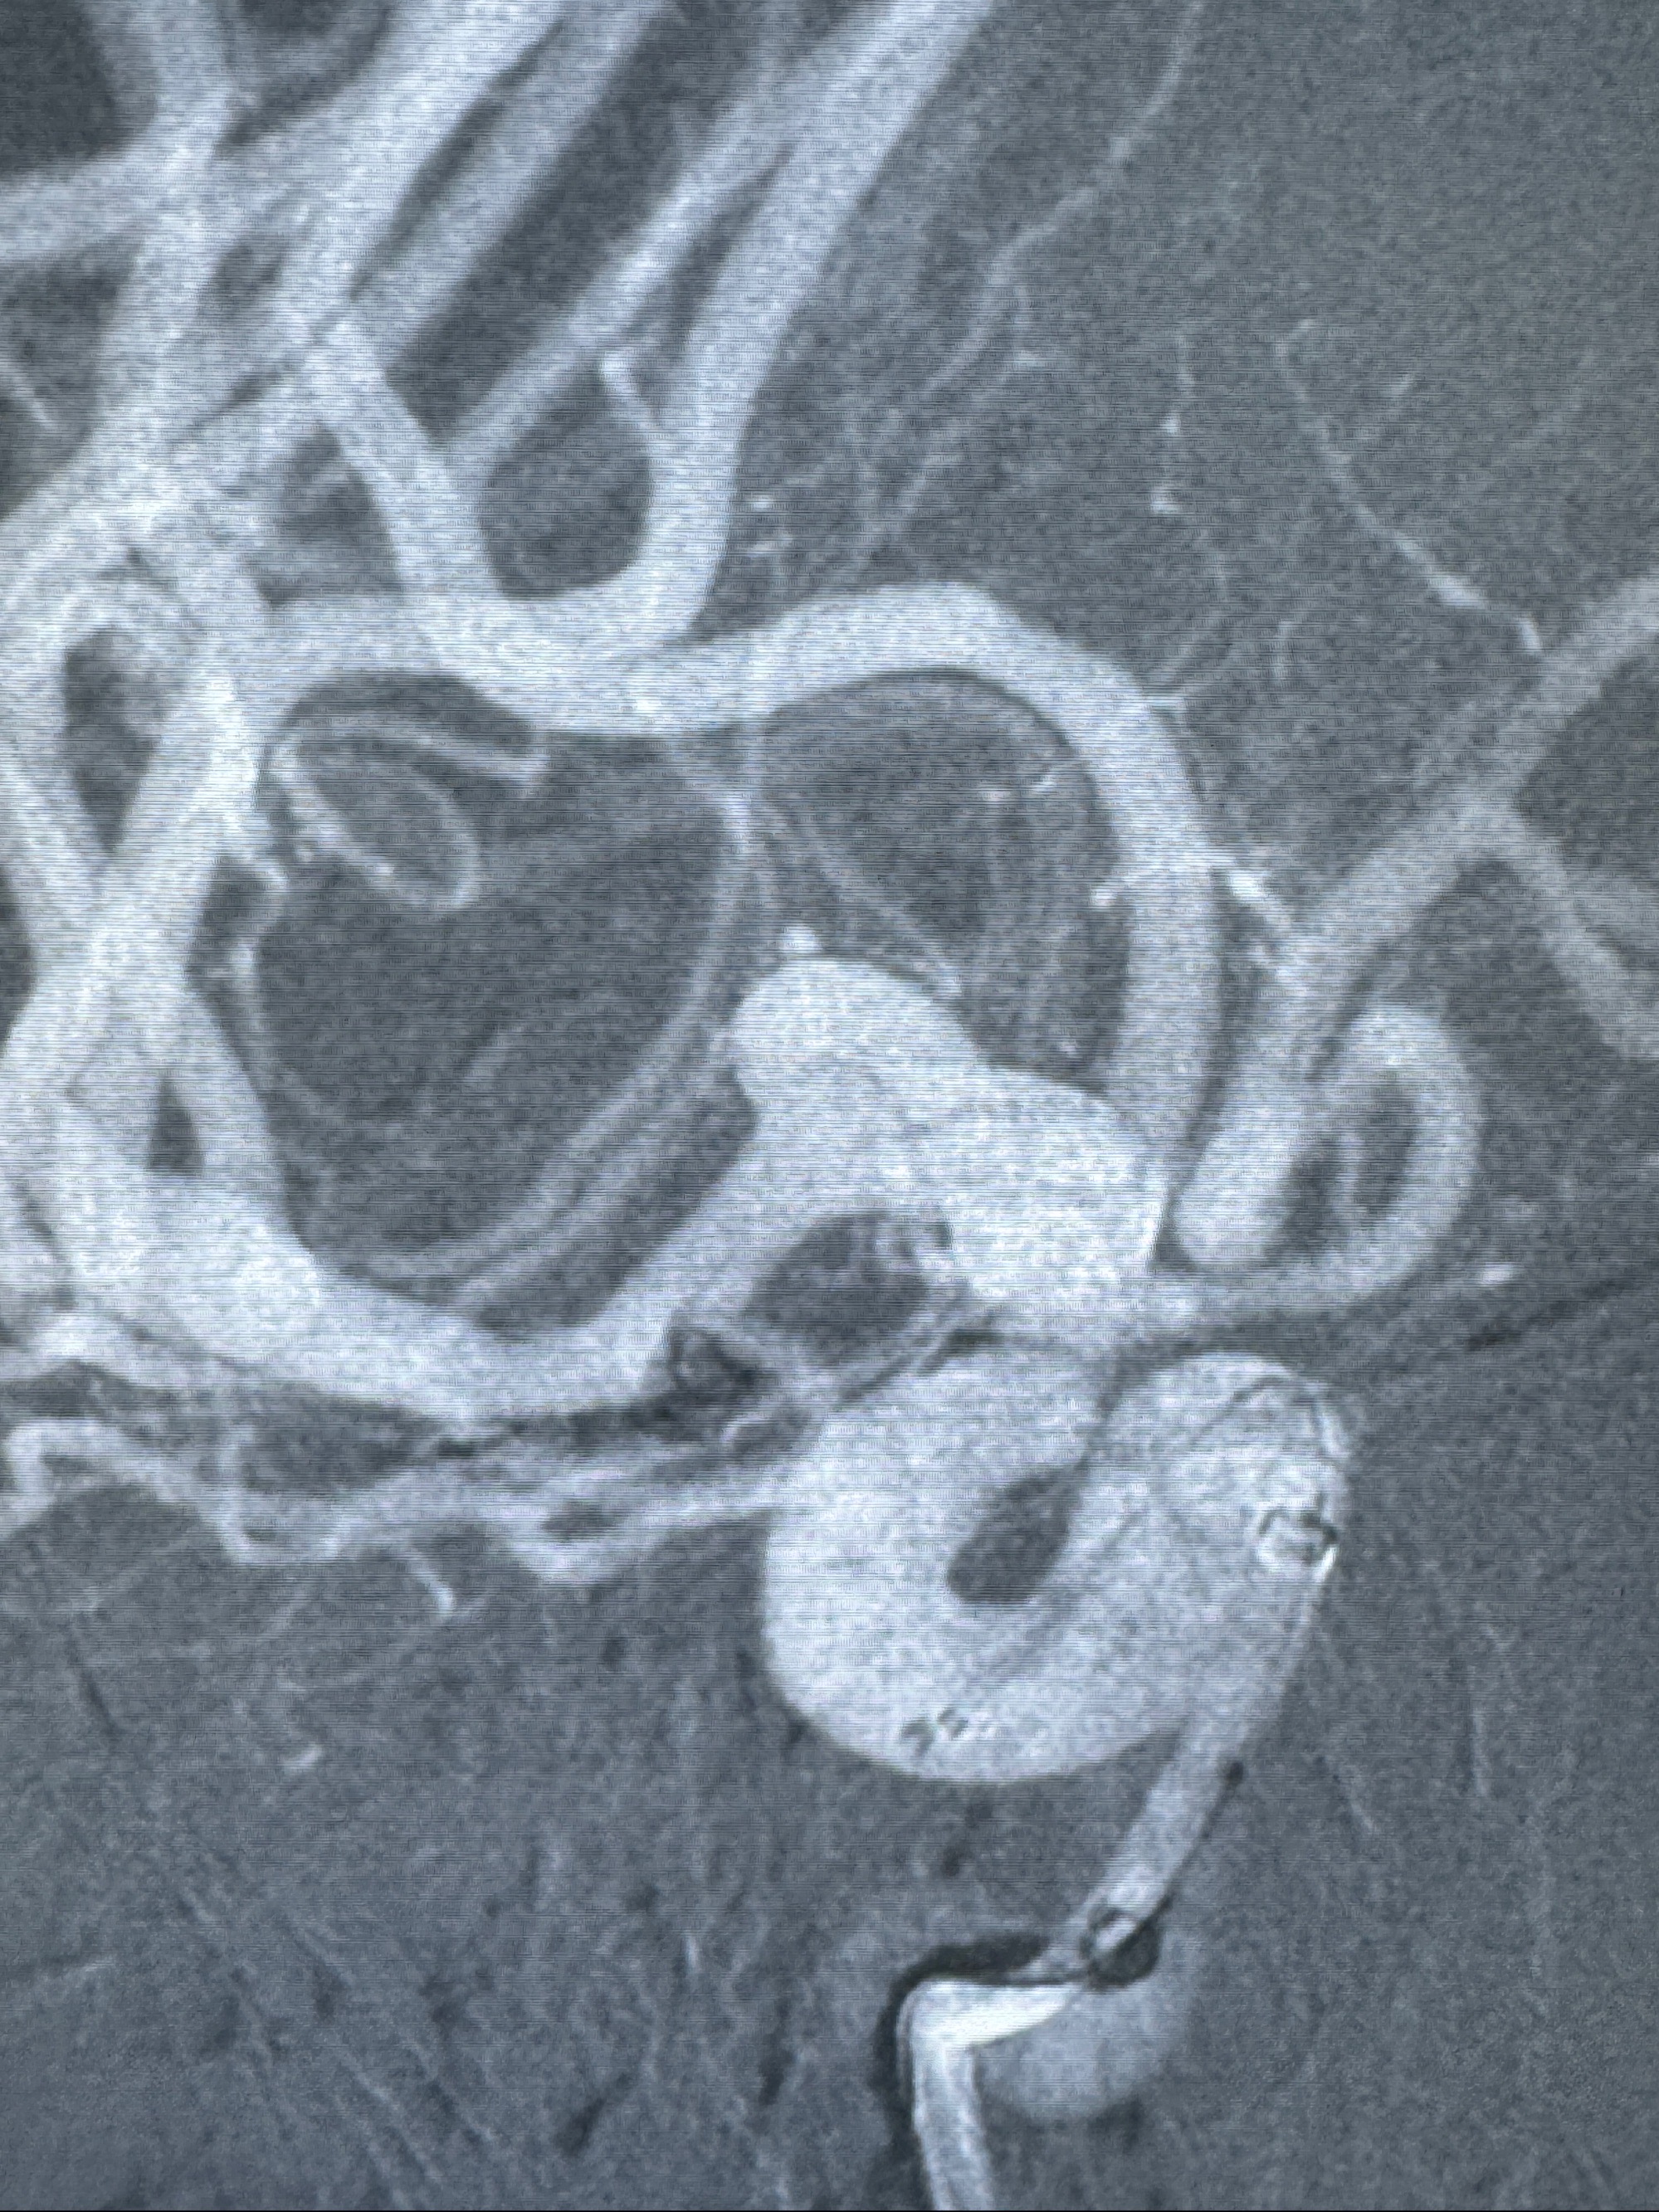

2023-12-04全麻下行支架辅助治疗

S-AB4-20mm

麻醉苏醒佳,遵嘱动作

术后即刻CT